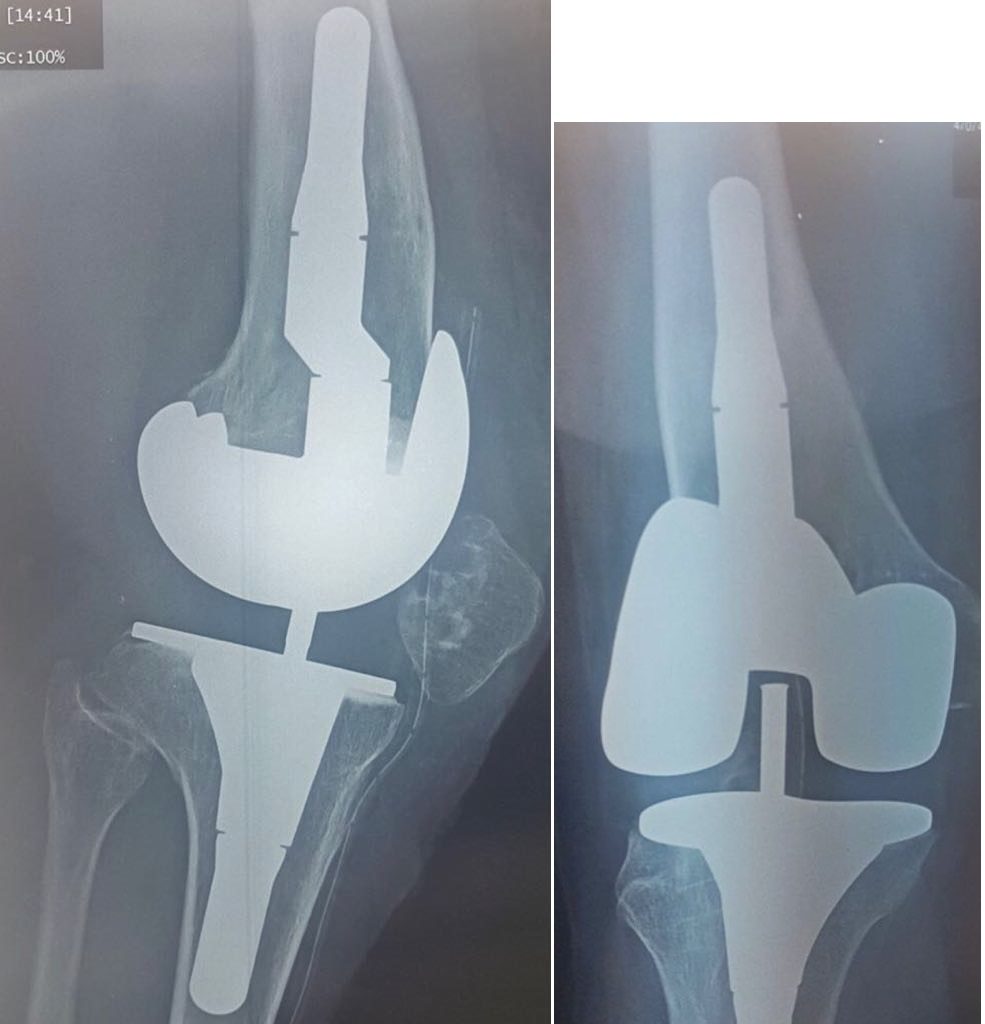

Gonarthrose sur Genu valgum

Cliquer sur une photo pour défiler la collectionGonarthrose sur Genu valgum avec distension du plan ligamentaire interne

Gonarthrose sur Genu valgum avec distension du plan ligamentaire interne